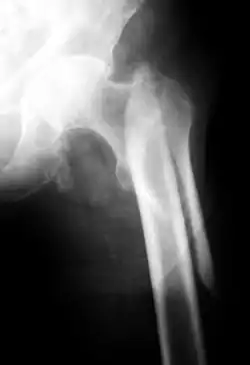

Eine lange Spiralfraktur des proximalen Oberschenkels

Auf kürzerer oder längerer Strecke spiralförmig verlaufende Frakturlinie. Entsteht durch indirekte Gewalteinwirkung (Verdrehung der feststehenden Extremität). Häufig beim alpinen Skisport.